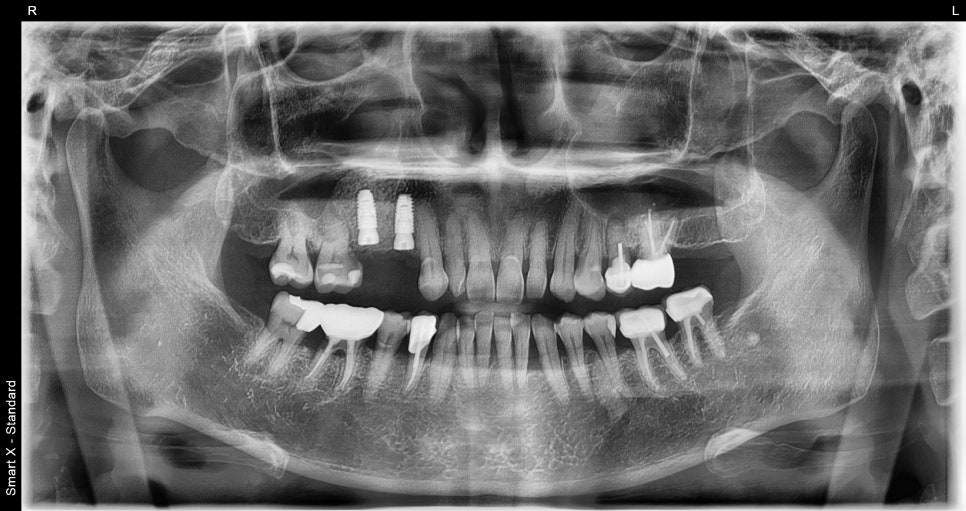

The examination showed that the jawbone had weakened significantly,

making it difficult to preserve the natural tooth,

and it was decided to restore function through implants.

The patient in their 60s also learned through these tests

that “the bone needs to be reinforced before placing the implant.”

Previous image

This is because the amount, structure, and gum condition of the bone

are different for each patient.